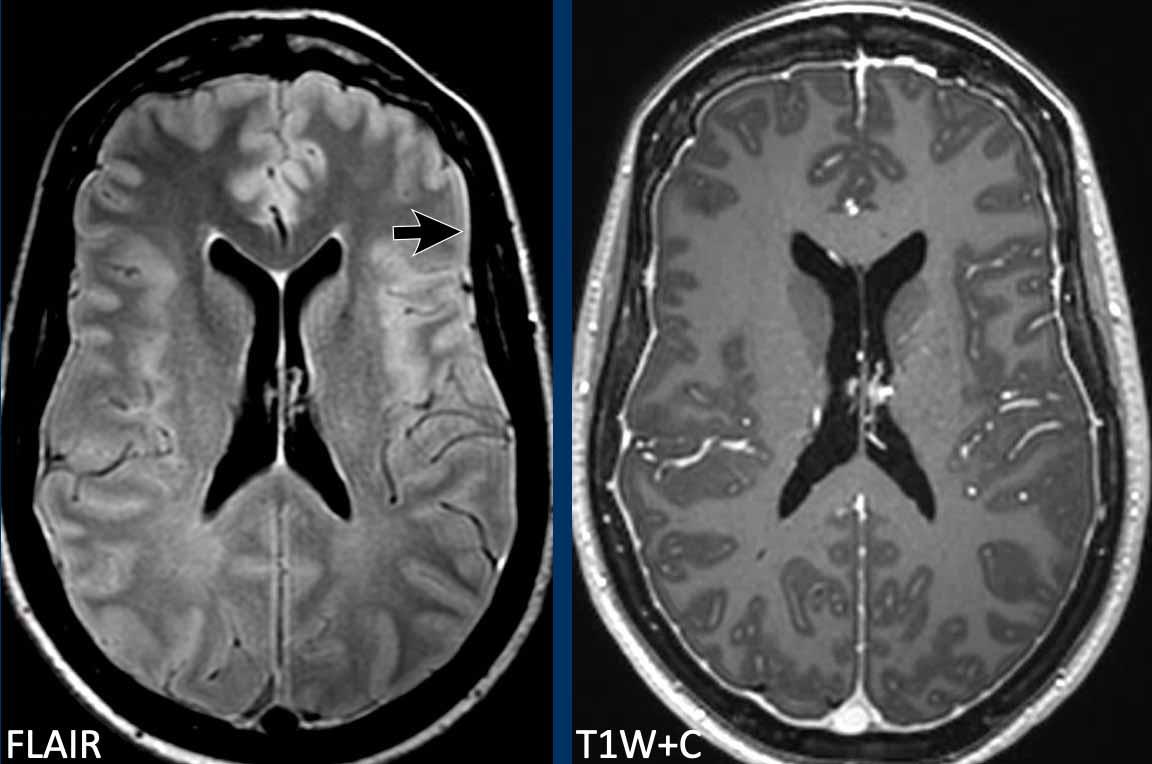

Dày màng cứng lan tỏa đều đặn đôi khi có thể thấy trên chuỗi xung FLAIR (mũi tên) nhưng dễ nhận thấy hơn trên chuỗi xung T1W sau tiêm thuốc tương phản từ.

Chuỗi xung T1W 3D sau tiêm thuốc tương phản từ và FLAIR axial: Đây là hình ảnh của một bệnh nhân có biểu hiện đau đầu và rối loạn nhận thức trong bệnh cảnh hạ áp lực nội sọ tự phát (SIH).

Hãy quan sát kỹ các hình ảnh trước khi tiếp tục đọc.

Hình ảnh

- Tràn dịch dưới màng cứng hai bên trên chuỗi xung FLAIR axial (đầu mũi tên).

- Giãn tĩnh mạch và xoang tĩnh mạch màng cứng với bờ dưới lồi của xoang ngang (mũi tên đen).

- Trung não bị võng xuống và khoảng cách thể vú – cầu não giảm.

Dấu hiệu hình ảnh

- Trung não bị võng xuống trên chuỗi xung T2W mặt cắt ngang.

- Ứ máu tĩnh mạch với bờ dưới lồi của xoang ngang.

- Màng cứng dày và ngấm thuốc.

- Giảm khoảng cách thể vú – cầu não.

Kết luận

Hạ áp lực nội sọ tự phát.